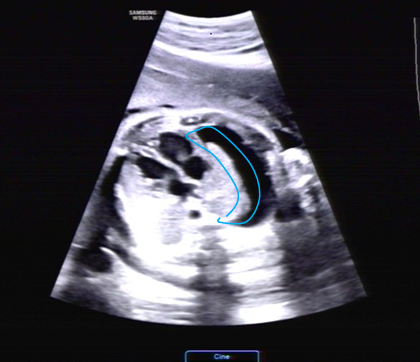

近日,懷孕38周的劉女士在當(dāng)?shù)禺a(chǎn)檢時(shí)發(fā)現(xiàn)胎兒右側(cè)大量胸腔積液,右側(cè)胸腔幾乎被“水”填滿,輾轉(zhuǎn)當(dāng)?shù)囟嗉裔t(yī)院均認(rèn)為預(yù)后不良,建議放棄胎兒。

經(jīng)過(guò)評(píng)估,劉女士的寶寶屬于孕晚期突發(fā)的單側(cè)大量胸腔積液,已經(jīng)對(duì)胎兒心臟和肺產(chǎn)生了壓迫,如不及時(shí)解決,后續(xù)胎兒可能出現(xiàn)水腫,隨時(shí)有生命危險(xiǎn)。

![微信圖片_20200806155248[1].jpg](/upload/image/20201025/16035892954560911.jpg)